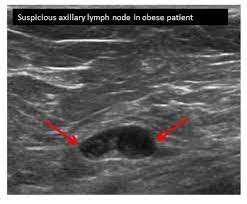

Inflammatory breast cancer, also known as carcinomatous mastitis, t4d, or pev 2 or 3, is the only real therapeutic emergency in breast oncology, given the high risk of metastasis, the reason for the most unfavourable prognosis of all breast cancers.it must consequently be diagnosed rapidly, and imaging examinations must in no case delay therapeutic management. The peak age at presentation may be comparatively younger than with other types of breast cancer 7. Ultrasound is not used on its own as a screening test for breast cancer. They're often easy to move around (mobile) and may be tender. Ultrasound may be particularly useful in detecting abnormalities in patients with dense breasts.

Ultrasound may be particularly useful in detecting abnormalities in patients with dense breasts. Finding breast lumps and seeing change in the size and shape. Ultrasound does not use or. Women or men who develop any of the inflammatory breast cancer early signs should seek medical care immediately to ensure timely treatment. The sound waves pass through the breast and bounce back or echo from various tissues to form a picture of the internal structures of the breast.

Computer Aided Assessment Of Tumor Grade For Breast Cancer In Ultrasound Images from static-01.hindawi.com Density is a term used to describe breast tissue that has many glands close together. Epidemiology these account for ~1% of breast cancers. Looks larger, thicker or heavier. That said, ultrasound is an extremely fast and powerful tool. Ibc is a rapidly progressive, aggressive form of breast cancer associated with a low overall survival rate. Is tender, aches or feels painful. Finding breast lumps and seeing change in the size and shape. Tubular carcinoma of the breast is a subtype of invasive ductal carcinoma (idc).